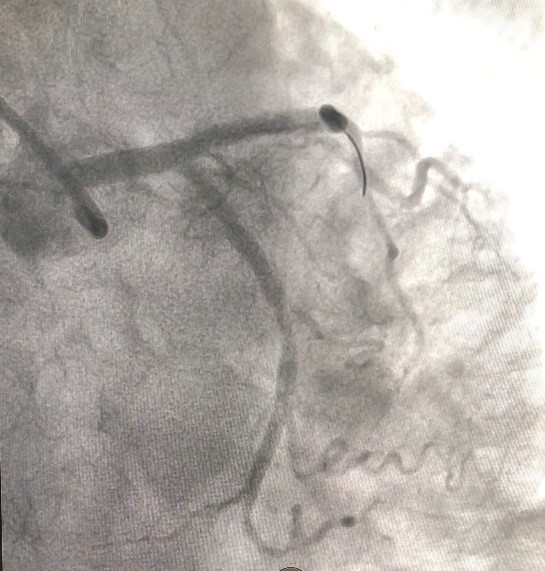

Sau xử trí cấp cứu huyết áp của người bệnh đã tăng lên 110/70mmHg, nhịp tim ổn hơn, được chuyển vào phòng can thiệp Khoa Can thiệp Tim và Mạch máu để tiến hành chụp động mạch vành qua da, kết quả cho thấy hẹp gần tắc đoạn gần động mạch liên thất trước. Kíp can thiệp đã nong bóng và đặt 1 stent phủ thuốc vào vị trí tổn thương.

![]() |

| (Hình ảnh: Hẹp gần tắc động mạch vành trước can thiệp) |